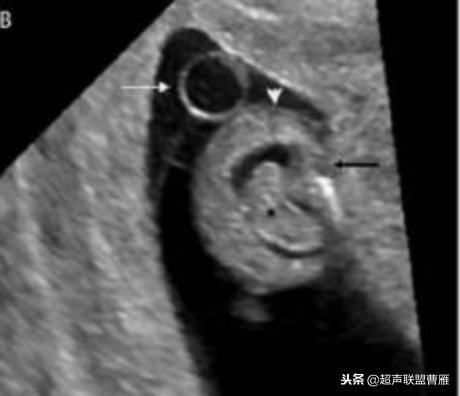

真实的卵黄囊、胚体及羊膜腔形象

一个孕囊有两个卵黄囊,单卵双胎。

正常宫内胚胎组织、卵黄囊

卵黄囊 羊膜囊 小胎儿雏形 (卵黄囊直径8.5mm)